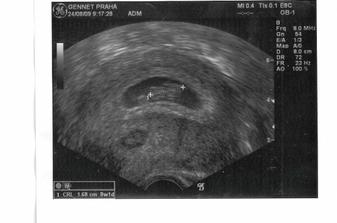

Dnes 25.9.2009 musel být ukončen kraťounký život našeho vytouženého mimíska. Kvůli závažné vývojové vadě neslučitelné se životem. Sbohem, broučku. Moc jsme se na Tebe všichni těšili. Moc jsme to oplakali. Snad se ještě někdy setkáme. Máma, táta, ségra a brácha.